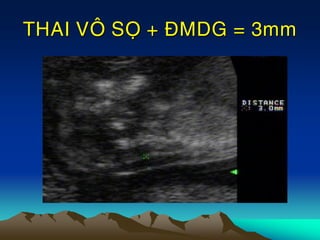

2. Ño ñoä môø da gaùy thai 11-14 tuaàn:

Bình thöôøng ÑMDG< 2.5-3mm

THAI VOÂ SOÏ + ÑMDG = 3mm

THAI VOÂ SOÏ+ ÑMDG = 3mm